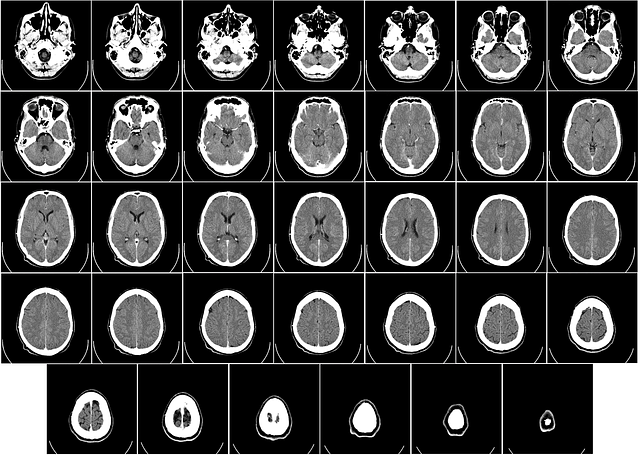

뇌하수체 선종, 두개인두종, 뇌수막종등 뇌의 종양에 대해 조직학적으로는 암이 아니지만 보험약관상 암으로 볼수 있느냐 VS 없느냐에 대해 분쟁이 많다는것은 잘 알려진 사실입니다.

뇌하수체종양의 진단코드가 중요하냐는 질문을 많이 받습니다. 질병분류번호는 아래 사례에서와 같이 D코드입니다. 보통 암이라하면 C코드에 해당하는데 D코드면 약관상 해당사항이 없습니다.